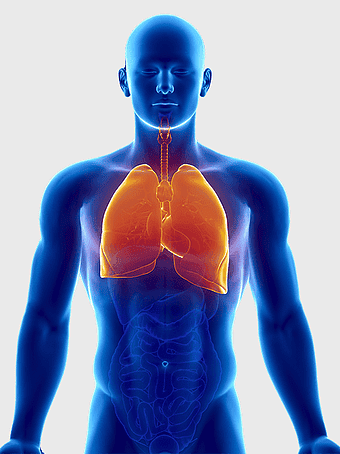

Pulmonary edema symptoms, chronic obstructive pulmonary disease diagram, kidney failure effects on lungs, pulmonary circulation illustration, lung disease diagnostic, respiratory health visuals, human anatomy respiratory system, PNG

- pulmonary edema symptoms

- chronic obstructive pulmonary disease diagram

- kidney failure effects on lungs

- pulmonary circulation illustration

- lung disease diagnostic

- respiratory health visuals

- human anatomy respiratory system